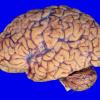

1A5 NCL (Case 1) gross 2 copy